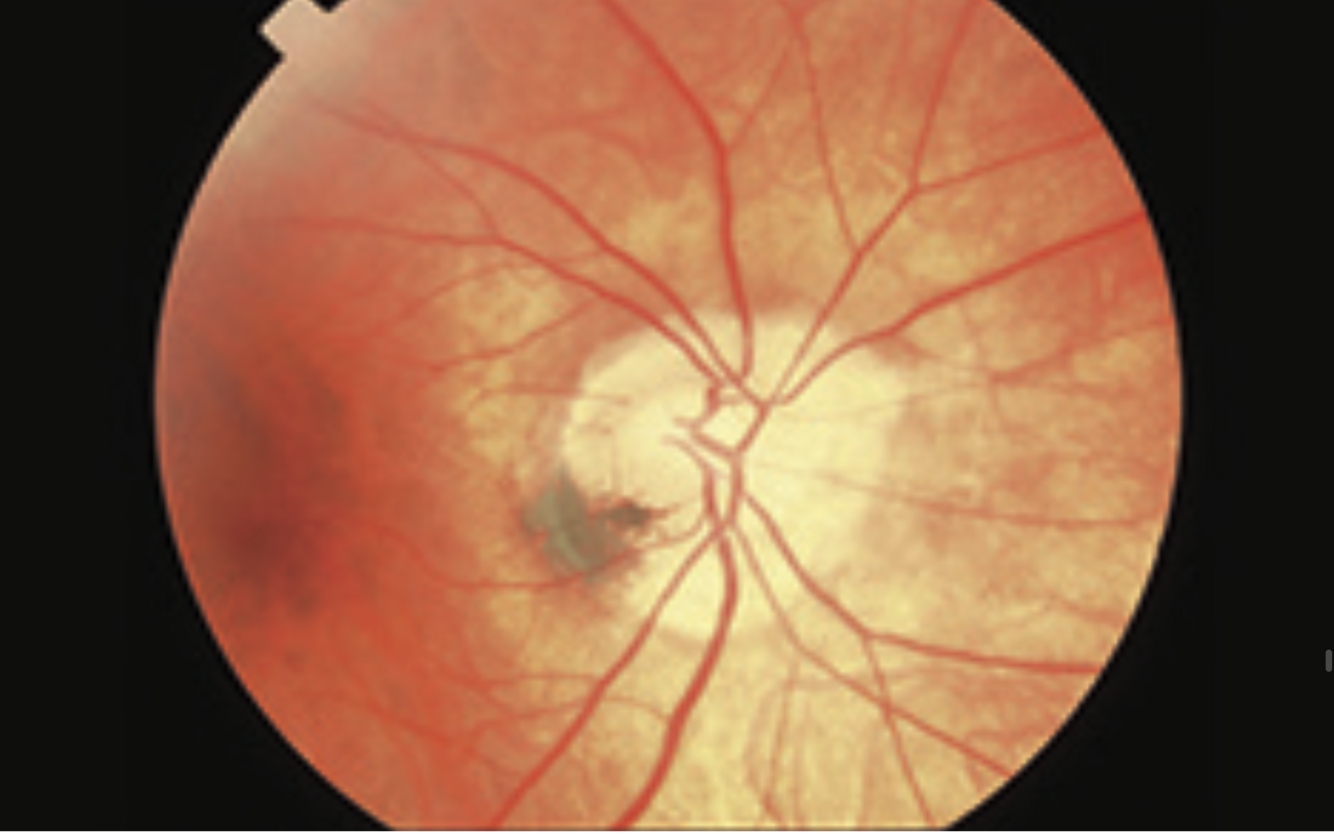

optic atrophy with macular scarring

glaucoma

- optic disc pallor

- macular scarring